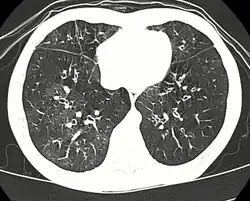

TDM bronchectasies, épaississants bronchiques[1]